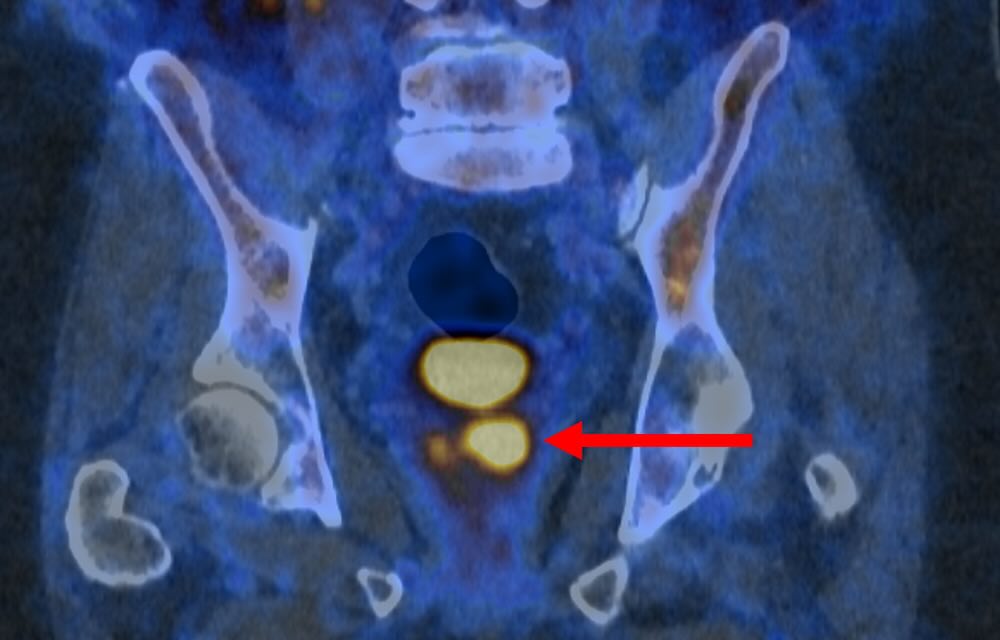

The state of the art imaging test uses a molecule that binds to prostate cancer cells, causing them to “light up in a remarkable way”—appearing as bright spots in the scanning image.

Their PSMA PET/CT scan identifies the more aggressive prostate cancer cells, which are potentially harmful and may need treatment—and could help reduce the risk of over-diagnosis by determining which cancers are low-risk and will never cause harm.

“PSMA PET/CT scanning makes prostate cancer cells light up in a remarkable way, particularly in more aggressive cancers,” said Dr. Buteau.